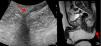

Imagen clínica y ecográfica del segundo paciente. 3a: nódulos violáceos con zona central erosiva en el glúteo izquierdo. 3b: banda hipoecoica dermohipodérmica correspondiente a tracto fistuloso que une la lesión visible con la piel perianal. También se aprecia engrosamiento dérmico y folículos dilatados (flecha roja).

El segundo paciente fue un varón de 32 años de edad, remitido desde el Servicio de Urgencias para descartar HS. Presentaba una placa indurada en el glúteo izquierdo de 6 meses de evolución, sobre la que asentaban 2 nódulos erosivos y exudativos (fig. 3a). No presentaba otras lesiones cutáneas en la zona o en el resto de los pliegues corporales. En el estudio ecográfico se describió una banda ancha hipoecoica dermohipodérmica que conectaba el orificio cutáneo visible con la piel perianal (fig. 3b). Además, asociaba un engrosamiento local de la dermis, dilatación de los folículos pilosos y el estudio doppler color era positivo en la periferia. Con la sospecha diagnóstica de fístula perianal como forma de presentación de una HS, se planteó tratamiento con infiltración de acetónido de triamcinolona y seguimiento en consulta de Dermatología. La resonancia magnética solicitada confirmó el recorrido dermohipodérmico del trayecto fistuloso.